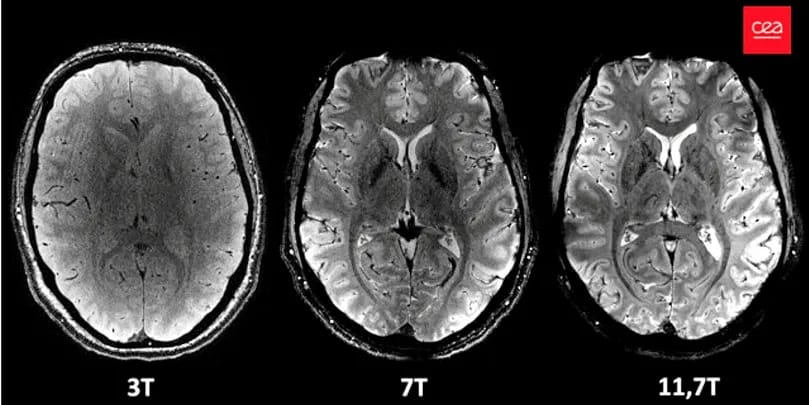

Les images sont les plus précises jamais publiées. Avec 11,7 teslas, l'IRM Iseult a une puissance bien supérieure aux outils de l'imagerie médicale jusqu'à maintenant utilisés dans les centres hospitaliers et les centres de radiologie (de 1,5 à 3 teslas) ou à d'autres appareils (à 7 teslas).